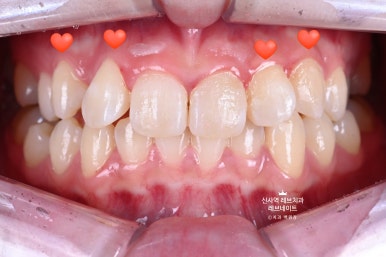

어쨌든 앞에서 보니, 확실히 다르더라구요.

아주 어려운 상황에서, 자연스러운 아름다움을 잘 찾아낸 것 같습니다.

입 안에서 보면 더 자연스럽습니다.

가로로 길어보이는 치아는 이 정도 웃어서는 보이지 않아요. ㅎㅎ

환자분이 정말 정말 만족하셨답니다.